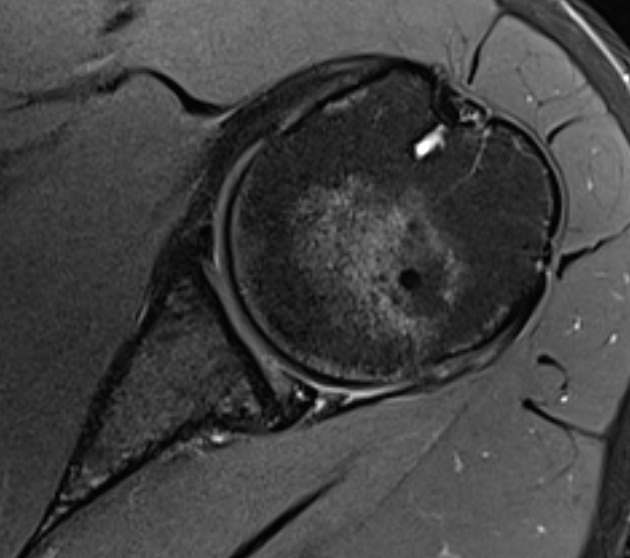

Posterior labral tear

Posterior labral tear

Kim lesion

- Kim lesion

- incomplete and concealed avulsion of the posteroinferior labrum

- superficial portion attached, deep portion detached

- labrum flat with loss of normal height resulting in retroversion of the chondrolabral glenoid